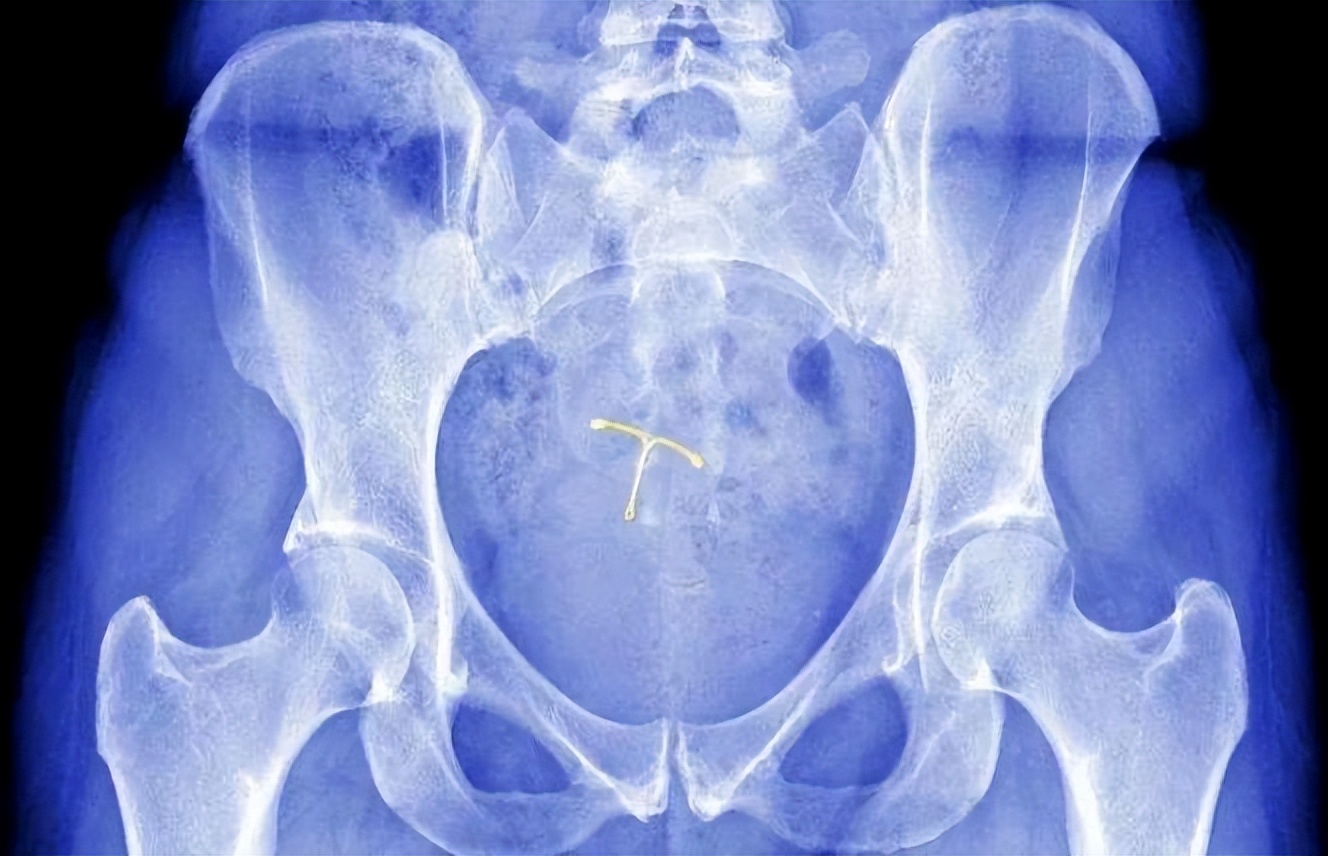

“上环”是指在女性子宫内放置避孕环,以达到避孕的目的。避孕环是一种T型装置,由柔软的塑料制成,上面缠绕着一根铜丝。

医生将避孕环插入女性子宫内,以阻止精子通过子宫颈进入子宫,从而达到避孕的效果,只需要在月经期间或月经结束后的7天内进行放置即可。

避孕环的使用期限结束后,需要将避孕环取出并更换新的避孕环。 相较于其他避孕方法,避孕环具有使用方便、避孕效果好、使用期限长等优点。